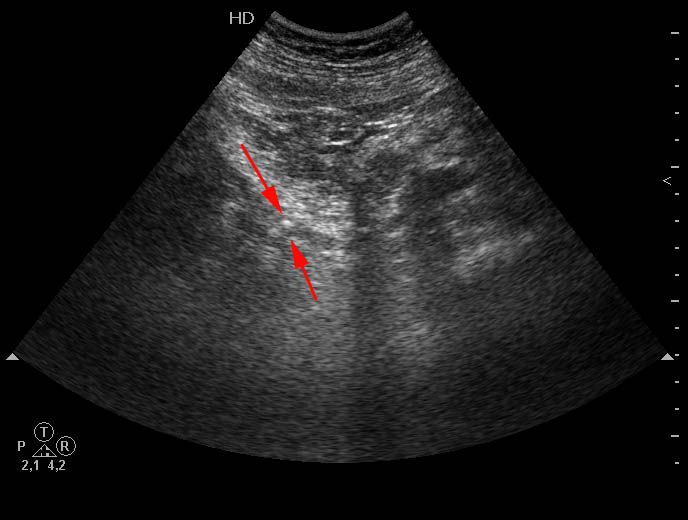

Пожилой мужчина с невыраженными болями в пояснице слева и микрогематурией.

УЗИ инспекция мочеточника. Sonographic inspection of an ureter